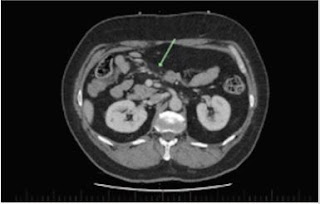

IgG4-related disease is a multi-system inflammatory disease that may affect most systems. Intracranial parenchymal disease is rare, reported only in case reports. Meeting diagnostic criteria typically requires biopsy, creating diagnostic and treatment uncertainty if biopsy not possible. We present a case of likely IgG4-related disease causing both mesenteric panniculitis and acute cerebellitis, a presentation not known to be previously documented.